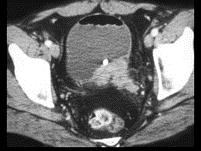

男,56岁,间歇性血尿半年余,请根据所示图像,选择最可能诊断 ( )A、膀胱癌B、膀胱息肉C、膀胱血块D、膀胱结核E、膀胱结石

问题 男,56岁,间歇性血尿半年余,请根据所示图像,选择最可能诊断 ( )

选项 A、膀胱癌 B、膀胱息肉 C、膀胱血块 D、膀胱结核 E、膀胱结石

答案 A